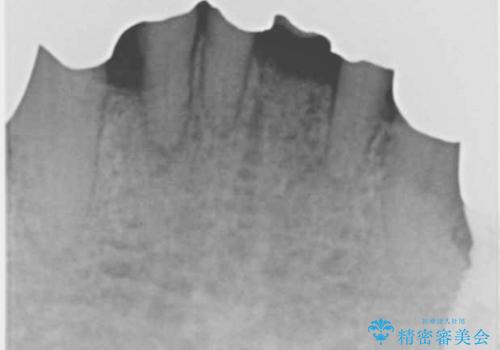

精査したところ、全顎的な重度の歯周病により下顎前歯に激しい動揺を認めました。

できるだけ自分の歯を残したいという患者様の強いご希望により、禁煙指導後再生療法(骨を増やす手術))を行いました。

再生療法から1年後リエントリー手術により骨の再生を確認し、骨外科処置(骨を平らにして歯周ポケットの根本的な改善を図る処置)を行ったのち、連結補綴を行いました。

骨吸収と動揺が著しい前歯1本(左下1)のみ抜歯しております。

再生療法と骨外科処置により、歯周ポケットは全周2mm以下に改善されました。